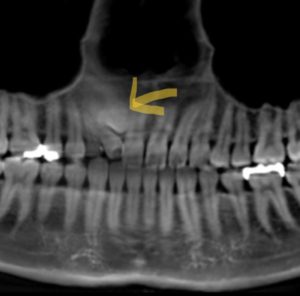

犬歯が水平に埋伏しています!矯正治療可能なの?

犬歯が水平に埋伏している状態は、矯正治療を考える上で重要な問題です。

この場合、犬歯が本来の位置に生えず、歯茎の中で横になっている状態を指します。

犬歯が水平に埋伏しているかどうかを確認するために、歯科医師は視診とともにX線写真を使って詳細な診断を行います。

これにより、埋伏している犬歯の位置、周囲の歯との関係、顎の骨の状態などが把握できます。